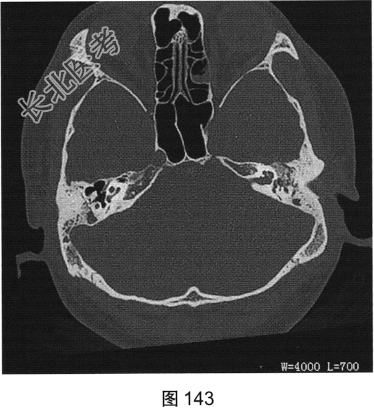

- [材料题] 患者男性,47岁,主诉间断左耳流脓10年,近期耳痛加重,既往无高血压,糖尿病及肿瘤病史。患者既往影像学检查如图143、图144所示。

- 简答题2、患者近期耳痛明显加重伴血性分泌物,再次进行了CT检查,CT影像显示患者鼓室腔内软组织影,鼓室盾板、鼓室盖及听小骨溶骨性骨质破坏,病变周围骨质毛糙。请问目前患者最可能的诊断是什么?